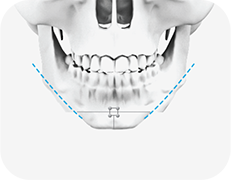

04

사각턱을 포함한 튀어나온 부분의 뼈를 절제

-

05

절제한 양쪽의 뼈를 제거하여 V라인 턱이 완성

* 뼈를 절제할 때 개개인에 맞는 추가수술법 피질골절제술, 근육절제술 시행